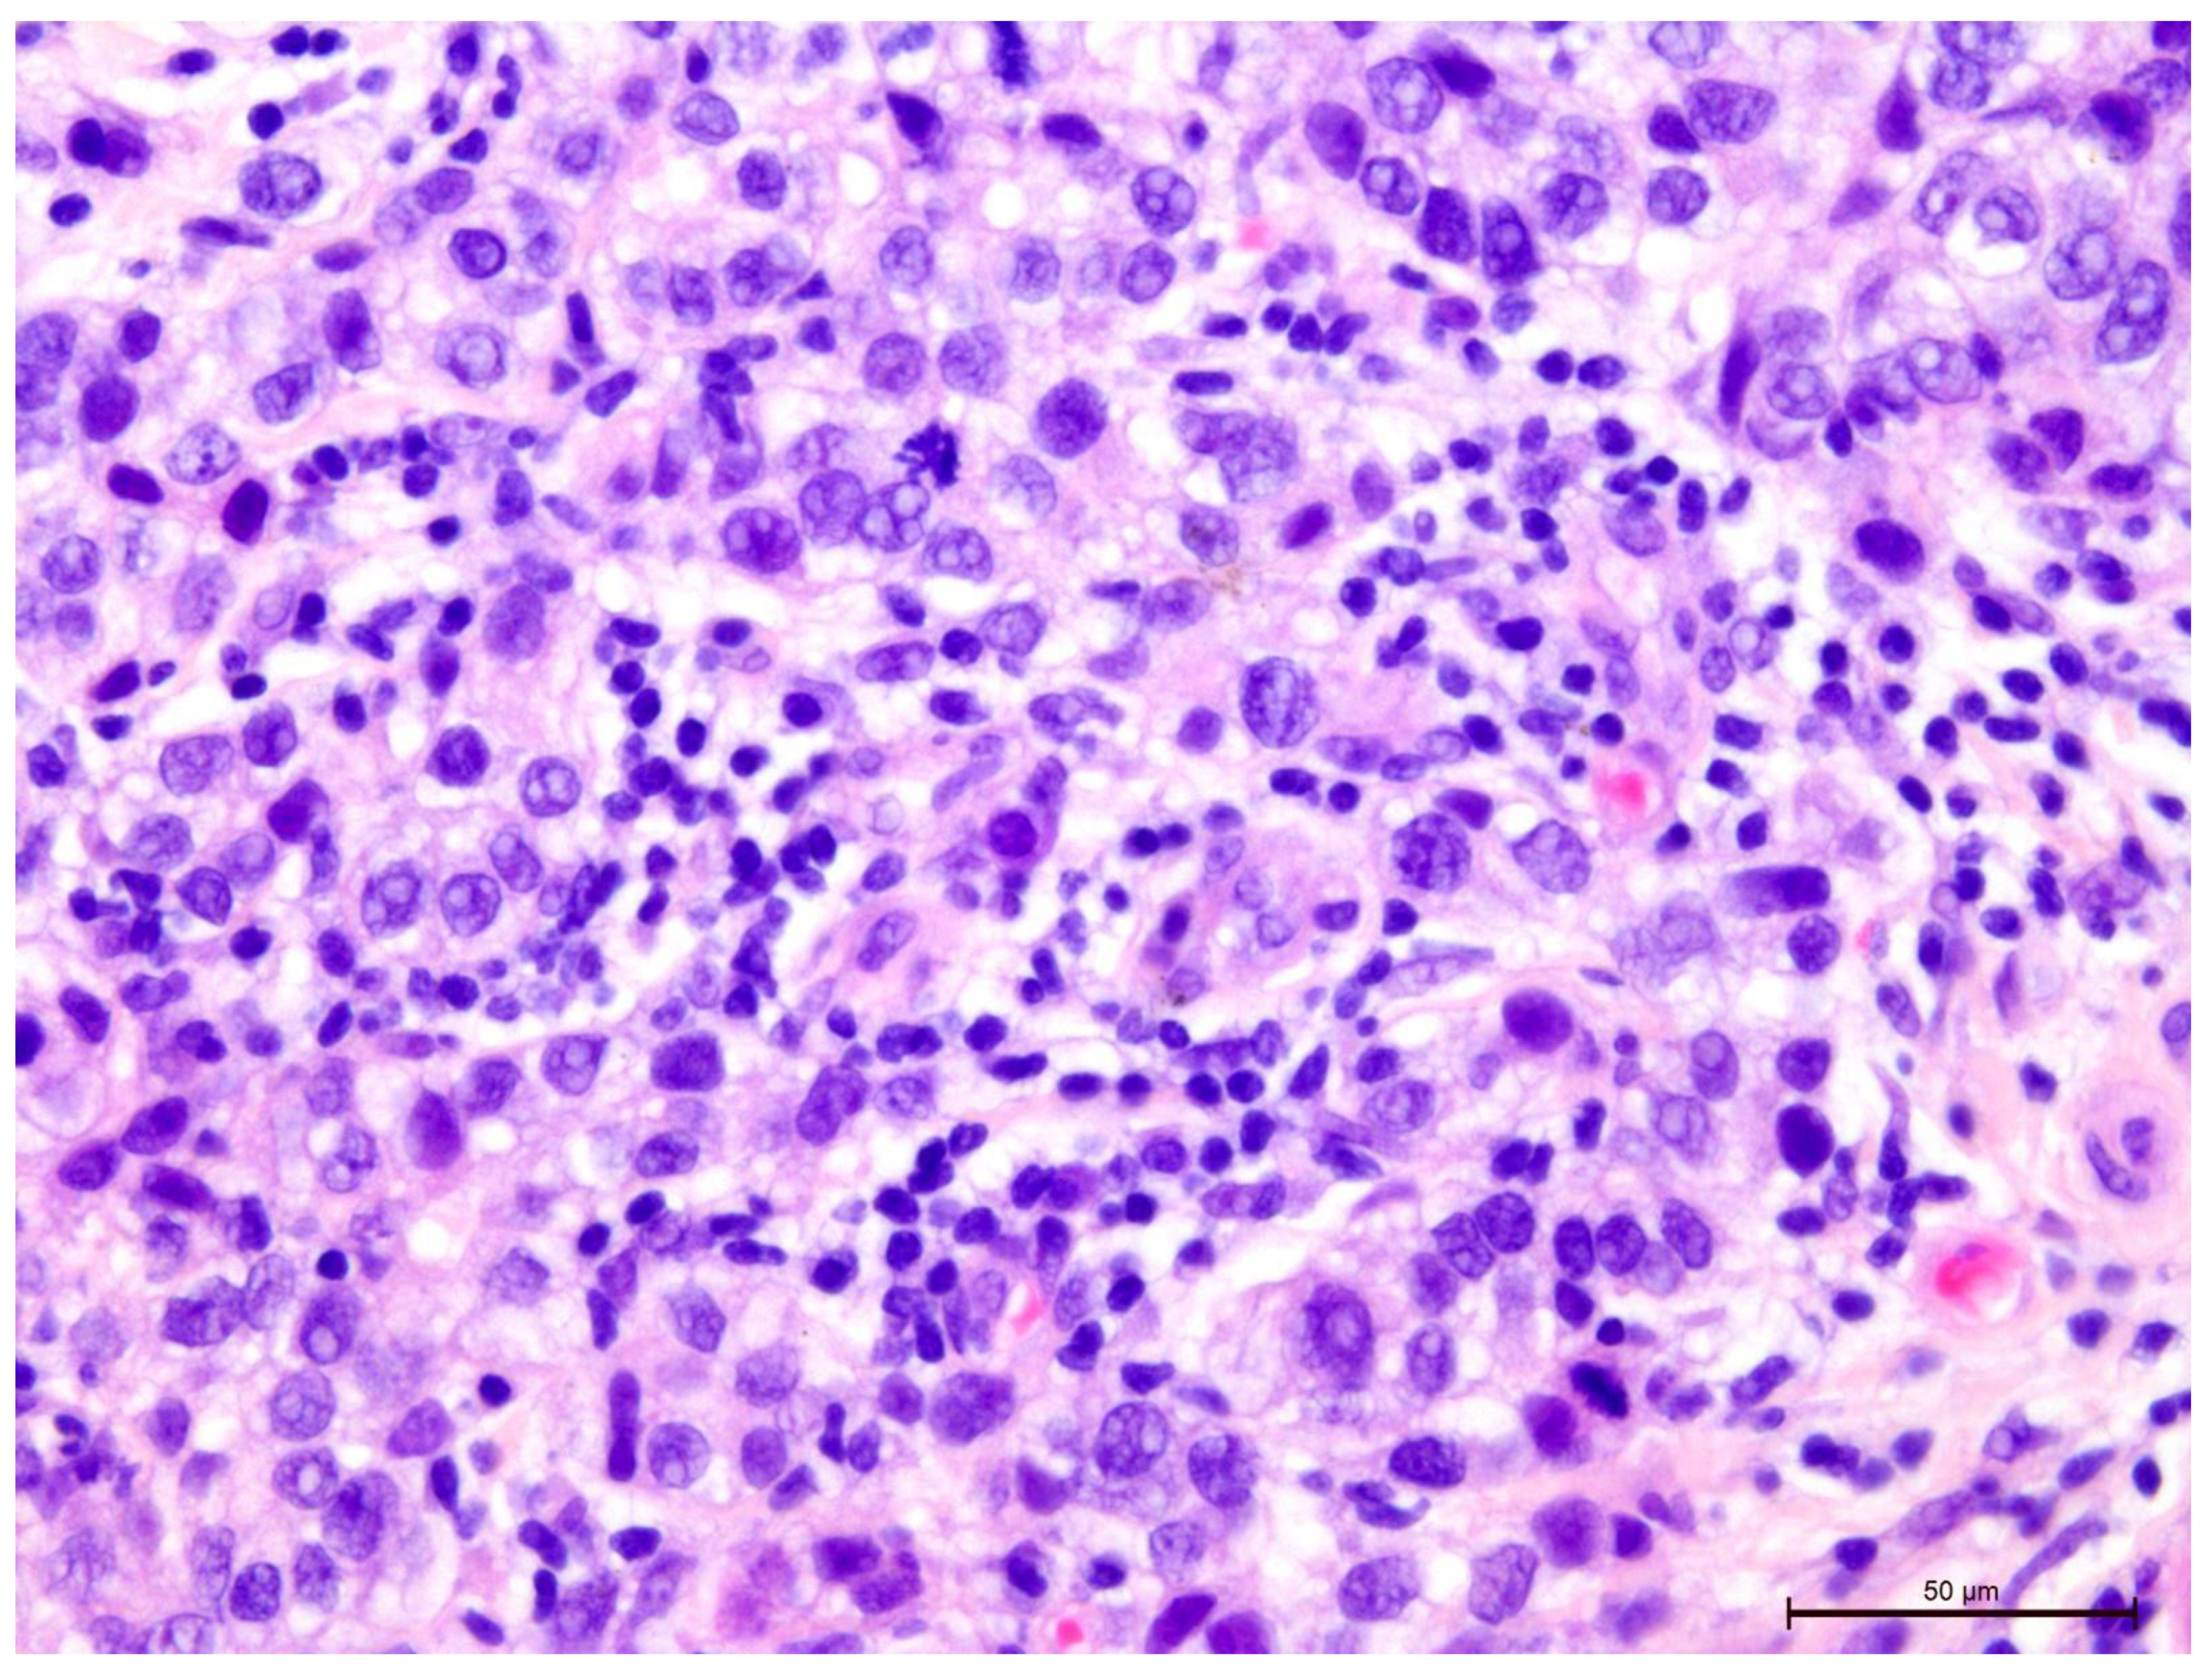

The T-lymphocyte infiltration in the tumor stroma was assessed according to the recommendations of the International Working Group on Immuno-Oncology of Breast Cancer Biomarkers (Figure 2, Figure 3, Figure 4, Figure 5, Figure 6 and Figure 7). The results are reported as the percentage of lymphocytes in the tumor stroma.

Figure 2. Invasive breast cancer with 70% T-lymphocyte infiltration in the tumor stroma, H&E staining, 630×.

Figure 3. Invasive breast cancer with 70% T-lymphocyte infiltration in the tumor stroma, H&E staining, 400×.

Figure 4. Invasive breast cancer with 70% T-lymphocyte infiltration in the tumor stroma, H&E staining, 200×.

Figure 6. Invasive breast cancer with 20% T-lymphocyte infiltration in the tumor stroma, H&E staining, area 400×.

Figure 7. Invasive breast cancer with 90% T-lymphocyte infiltration in the tumor stroma, H&E staining, area 400×.